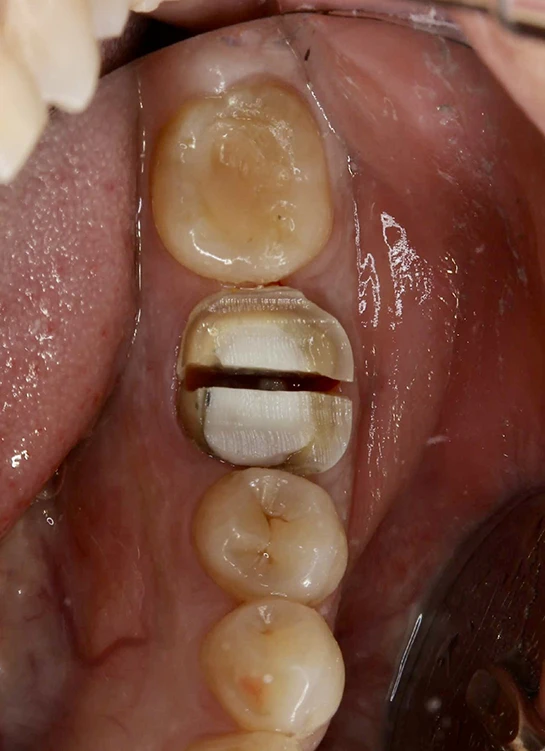

40代、女性、左下噛むと痛いこと主訴に来院され、インプラント治療を行いました。

| 診断結果 | 左下6番歯根破折 |

| 治療内容 | 抜歯即時インプラント |